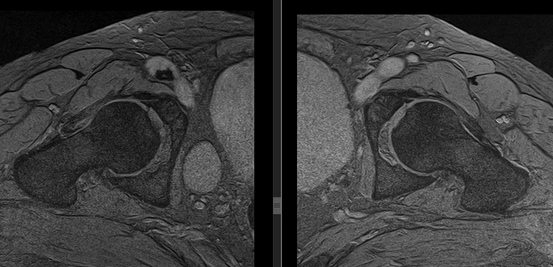

(Слева) МРТ Т1, аксиальный срез: у футболиста с болью после получения травмы, определяется гипоинтенсивный полулунный осколок задней стенки вертлужной впадины. Осколок перелома немного смещен.

(Справа) MPT, STIR, сагиттальный срез: у этого же пациента определяется выпот в полость сустава, отек головки бедренной кости спереди. Эти признаки указывают на ушиб с повреждением вышележащего хряща, а также на отек в месте перелома задней вертлужной впадины. Данные признаки служат критерием транзиторного заднего вывиха.